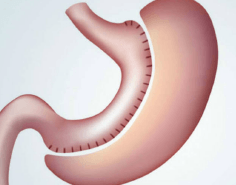

Manga Gástrica

Es un procedimiento en el cual se reduce la capacidad del estómago y se restringe la ingesta de alimentos al presentarse una saciedad temprana con pequeñas cantidades de comida, además de que se disminuye la secreción de hormonas que producen hambre . Se realiza mediante mínima invasión por Laparoscopía, y consiste en engrapar y cortar el estómago en toda su longitud quedando de forma tubular, de este modo se reduce el tamaño y la capacidad gástrica de 850 ml a 150 ml aproximadamente.

Este procedimiento se realiza con la mejor tecnología quirúrgica disponible otorgando gran seguridad y permitiendo que el paciente el mismo día que es operado inicie la ingesta de dieta líquida, comience la movilización en las primeras horas posteriores a la cirugía y egrese a las 24-48 horas de la cirugía. Además, al ser un procedimiento laparoscópico, permite una rápida recuperación y retorno a las actividades cotidianas prácticamente de forma inmediata. La Manga Gástrica es una cirugía que genera excelentes resultados en pérdida de peso y logra el control o resolución de enfermedades asociadas, permitiendo disminuir la dosis o suspender la ingesta de medicamentos para el control de la glucosa, lípidos y presión arterial. Los resultados pueden variar en cada paciente y pueden estar determinados por el apego de los pacientes a las indicaciones médicas.